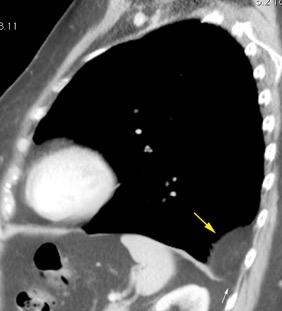

Mesotelioma epitelioide

La ocupación del espacio pleural por derrame (o obstrucción aérea) se acomoda con expansión aumentada de la caja torácica, especialmente en eje vertical. La consecuencia es aplanamiento e incluso inversión diafragmática.

Afzal S, Fatima K, Ambareen M. Antenatal ultrasound diagnosis of congenital high airway obstruction syndrome: a case report and review of literature. Cureus. 2019. Thoma R et al. Physiology of breathlessness associated with pleural effusions. Curr Opin Pulm Med. 2015

Wang JS et al. Changes in pulmonary mechanics and gas exchange after thoracentesis on patients with inversion of a hemidiaphragm secondary to large pleural effusion . Chest 1995